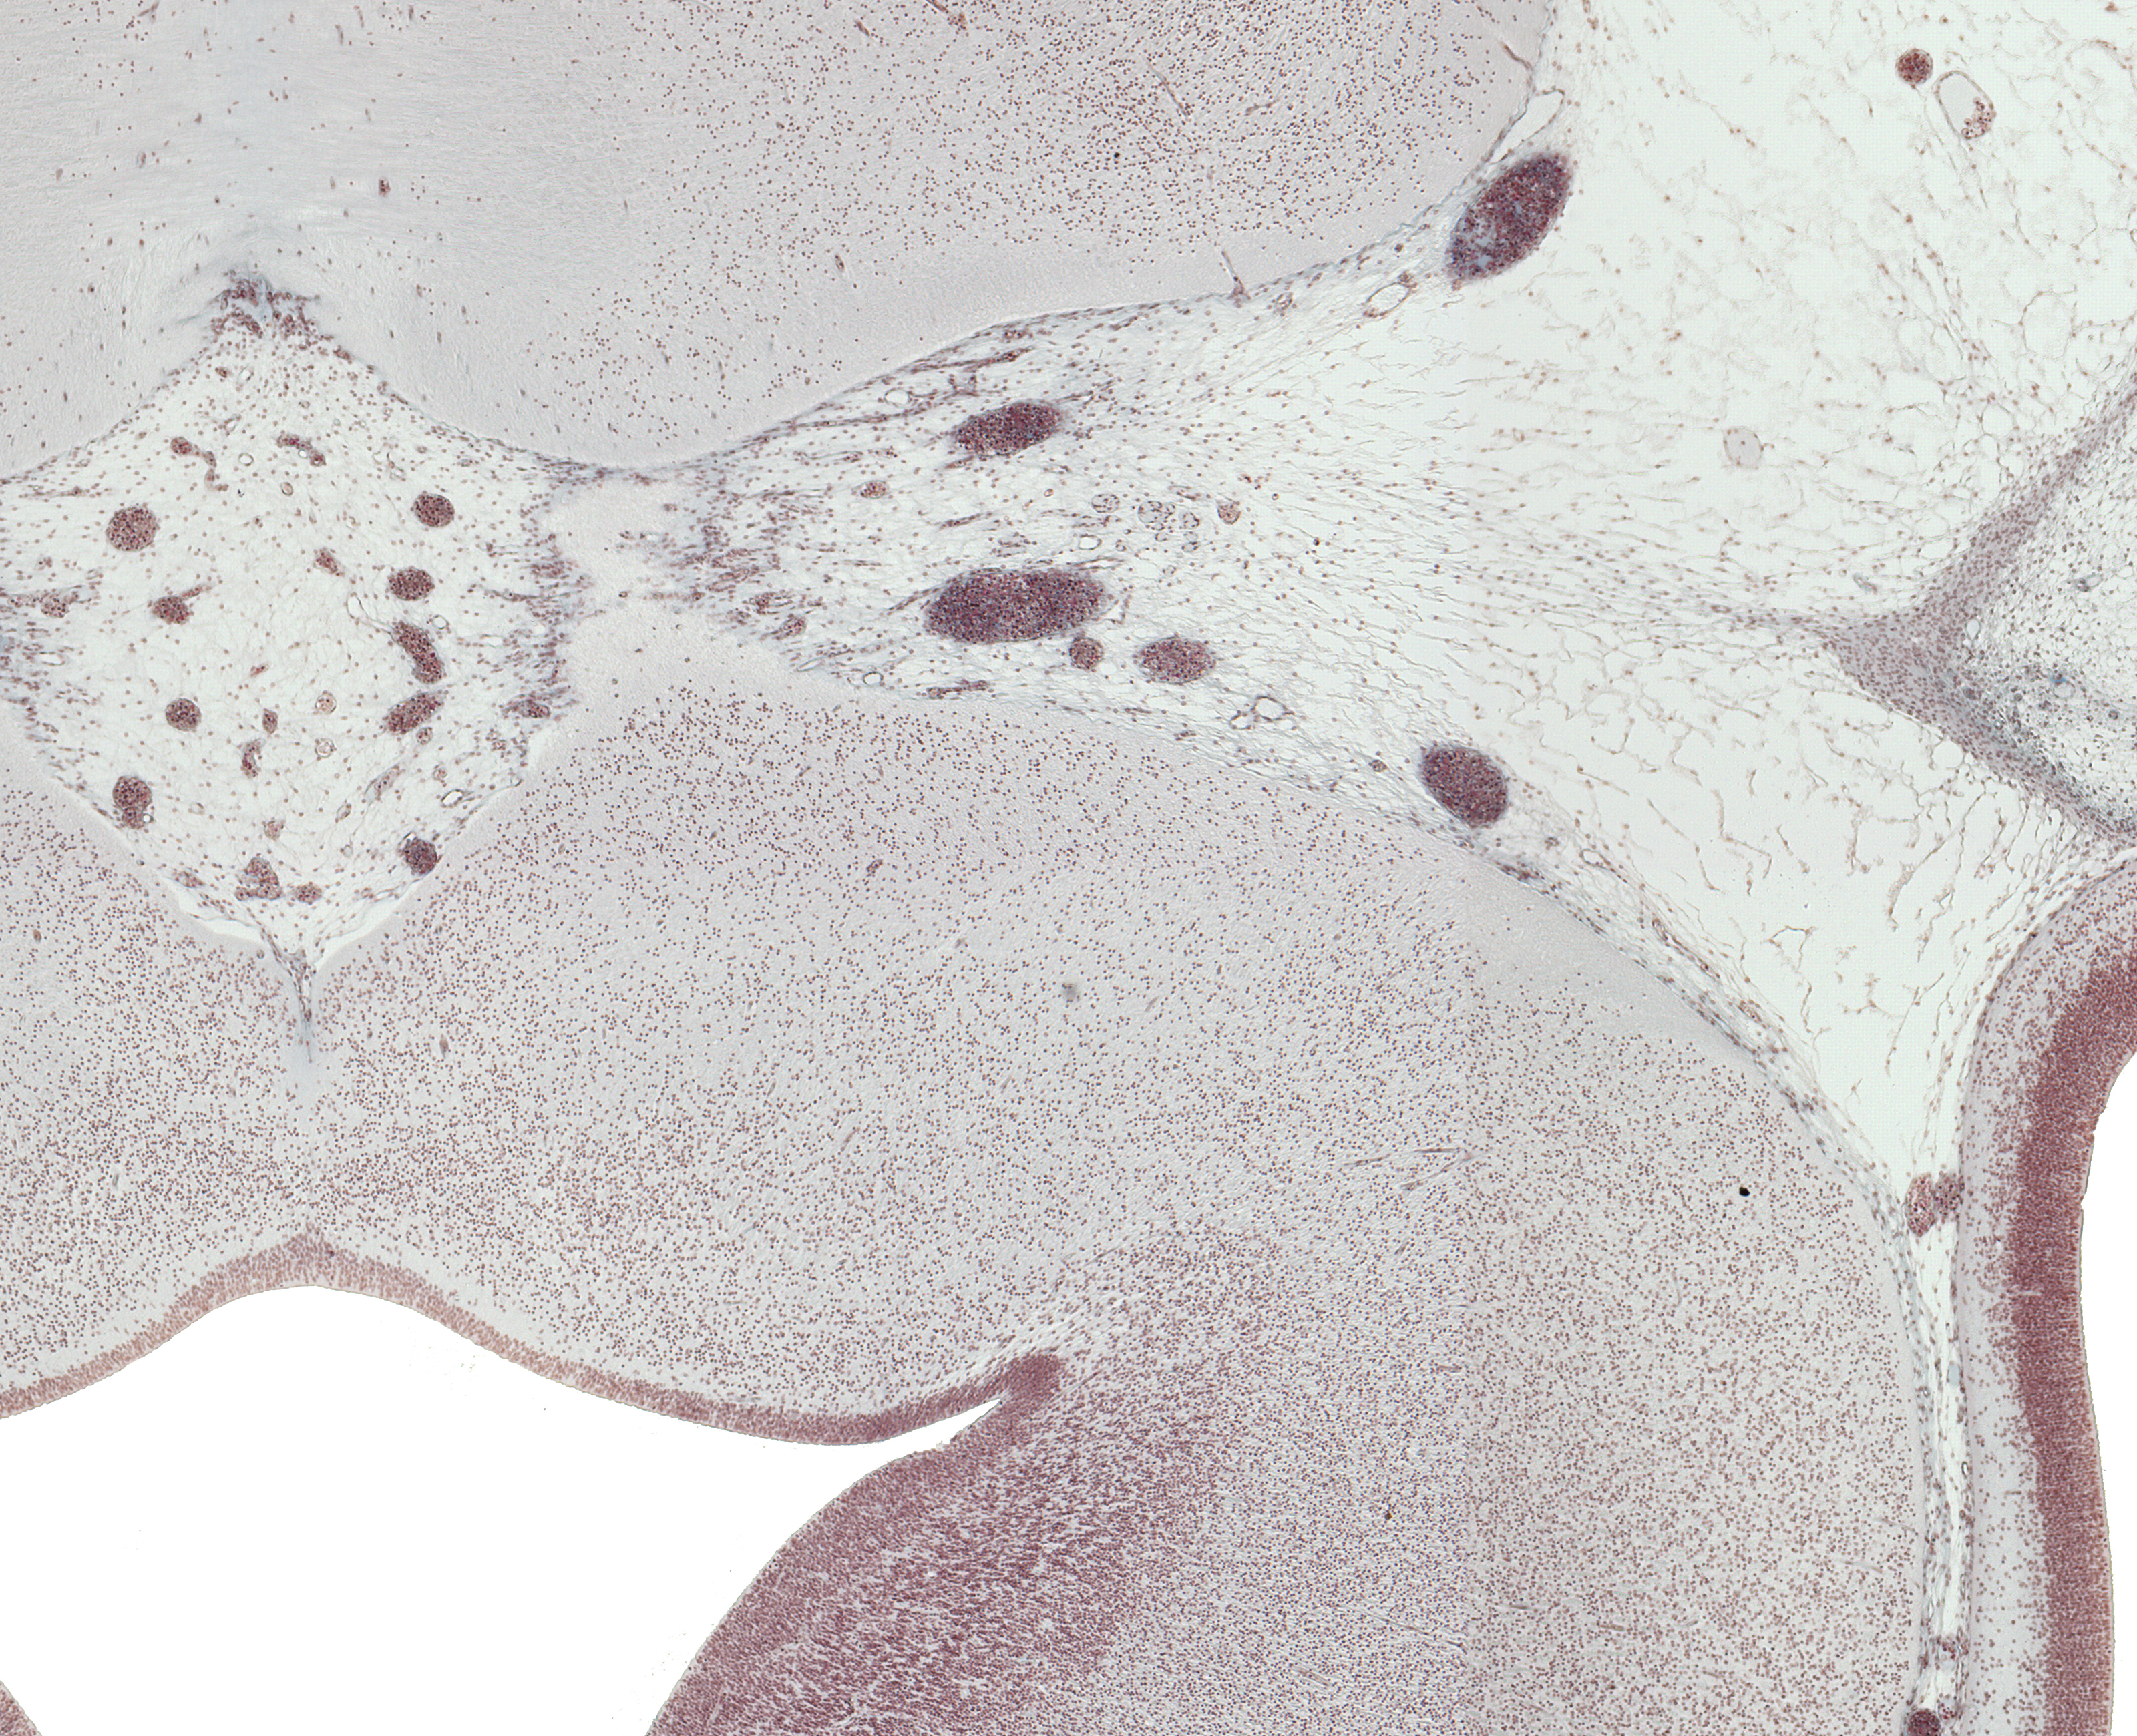

Tissue

–

Pyrimidal Tract Basis Pedunculi and CN III Rootlets

Carnegie Embryo #9226

Location:

30-01-01